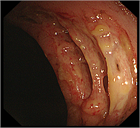

1. 患者背景、臨床症状からCMV腸炎を疑う場合は、組織採取が行える内視鏡検査が勧められる(推奨度1)

1. CMV腸炎診断のための内視鏡検査は、深部大腸まで観察し、潰瘍だけでなく、びらん、発赤、などの粘膜変化からも生検することが勧められる(推奨度2)